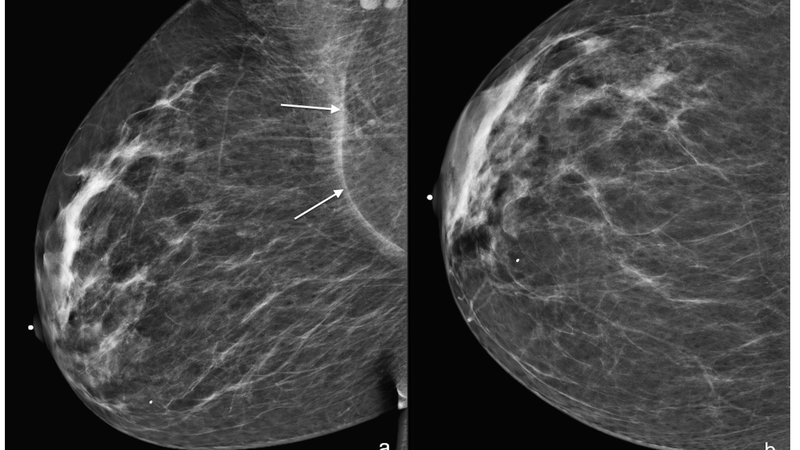

• Đi khám nội tiết: Người bệnh có thể đến thăm khám tại bác sĩ chuyên khoa nội tiết hoặc bác sĩ phụ nữ. Thông qua những kiểm tra lâm sàng, siêu âm hoặc làm mammogram thì bác sĩ có thể đánh giá được khối u của người bệnh.

• Nếu muốn phát hiện sớm dấu hiệu của hoại tử mỡ mô vú thì có thể đi siêu âm vú. Việc siêu âm còn giúp bác sĩ xác định được kích thước của khối u và đưa ra những lời khuyên cho người bệnh một cách phù hợp.